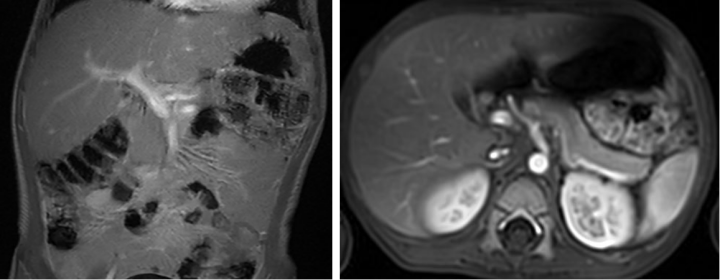

腹部MRI增强(2024.06.15):

神经母细胞瘤术后,左侧腹膜后术区周围见不规则片状液体信号影及数个低信号金属夹影;腹主动脉周围见少许条片状T1W低、T2W高信号影,增强后强化不明显

腹部MRI增强(2024.07.18):

神经母细胞瘤术后,左侧腹膜后术区见数个低信号金属夹影。